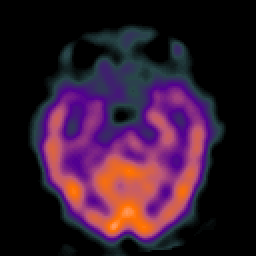

Alzheimer's Disease: SPECT/fMRI overlay -- Slice #3

[Home][Help][Clinical] Slice 3